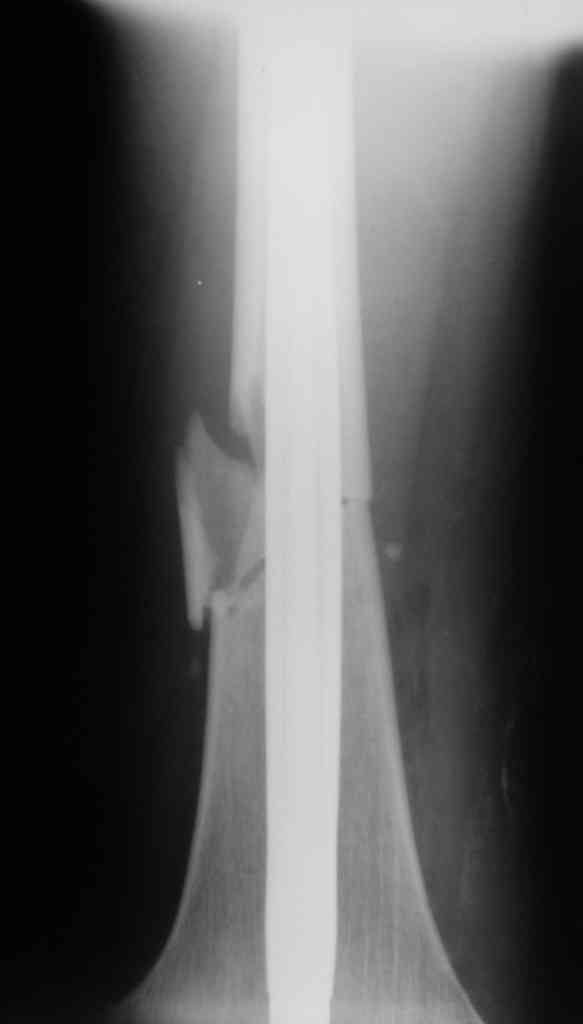

Дорогой Александр. Имею скромный опыт использования системы Fixion при переломах плеча, бедра и тибии. Всего 18 наблюдений с сентября 2006 г. Результаты отличные. Гвоздь индивидуален для каждого медуллярного канала. Легко имплантируется как в узкий, так и в деформированный канал. Это позволяет применять метод интрамедулярного остеосинтеза без ненужных потерь времени операции, флюороскопии и реально снижает крвопотерю и операционный риск. Удаление происходит без проблем. Особенно интересны больные с ипсилатеральными переломами бедра и голени.

В отношении ранней нагрузки при спиральных переломах лучше не торопиться. По данному случаю необходимо достигнуть исчезновения щели между штифтом и внутреним кортексом по Rg. А так картинка прекрасная - и длина сегмента и репозиция. Можно поздравить, коллега!

Да, спасибо за интересные иллюстрации. Получилось очень симпатично. На большеберцовой кости непременно надо было винты? Там же был торцовый упор, перелом в средней трети?

Это при раздувании гвоздя, или сейчас? Если второе, то я не понял. А так - давление повышали до 80 ата, перестали нагнетать, когда перестало снижаться меньше 70.

Спасибо, мы старались, чтобы первый блин не был комом.